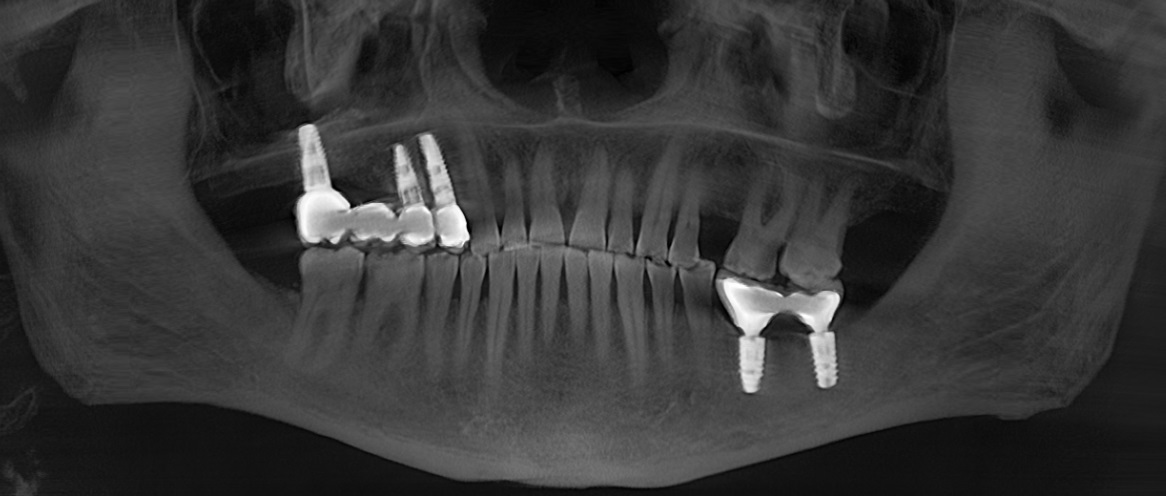

Пациент созрел на замену временных коронок постоянными на верхней челюсти справа и установку временных коронок на нижней челюсти слева:

Этот человек, как вы поняли, не поддавался объяснениям и «запугиванию», поэтому временные коронки были сделаны на металлическом основании. Они несколько прочнее.

Разницу в материалах можно видеть по белым полоскам в месте, где должна быть коронка. Если обычную временную коронку не видно, то при наличии металла на рентгеновском снимке его будет отчетливо видно.